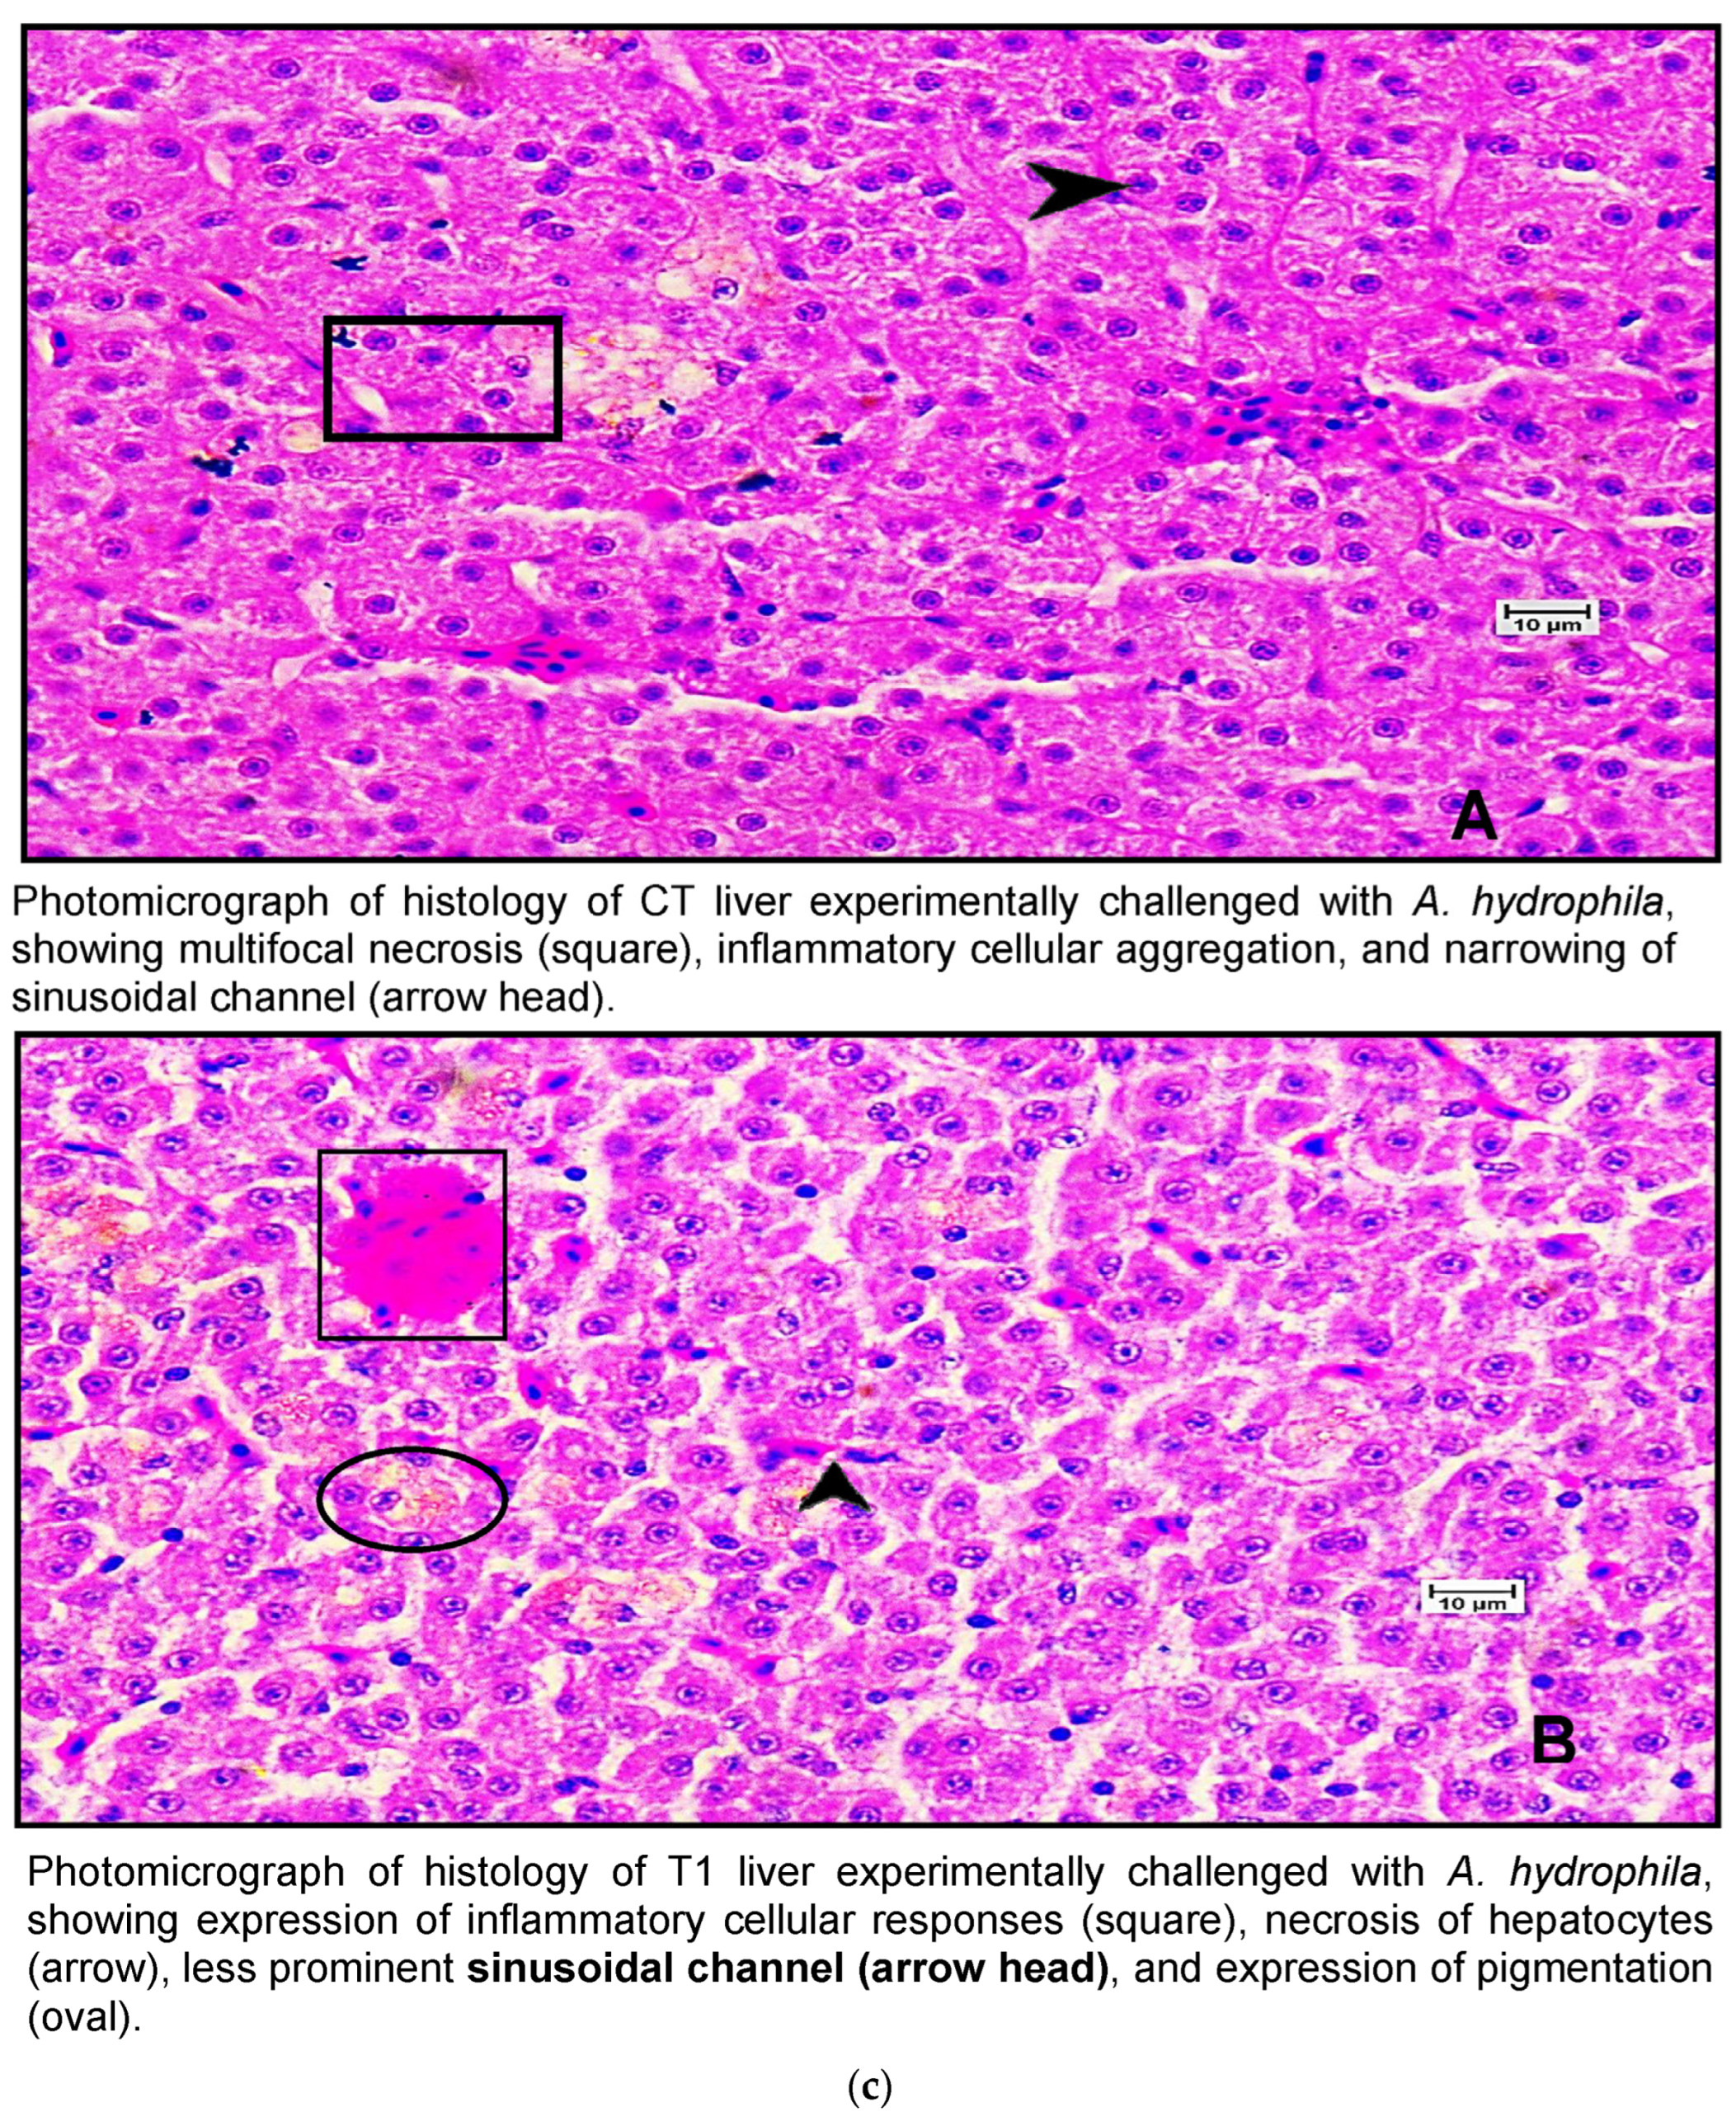

Figure 7.

(a) A photomicrograph of the livers of CT and T1 groups. (b) A photomicrograh of the livers of T2 and T3. (c) A photomicrograph of the livers of CT and T1 groups challenged with A. hydrophila. (d) A photomicrograph of the livers of T2 and T3 groups challenged with A. hydrophila. (e) A photomicrograph of the livers of CT and T1 infected with E. tarda. (f) A photomicrograph of the histology of the liver of T2 and T3 infected with E. tarda.

Histological examination of the livers of fish fed the control diet (CT) and the high-dose TABP diet (T3) revealed significant differences in the liver pathology (Figure 7a,b). The livers of fish fed the CT diet had a normal organization of polygonal hepatocytes, normal bile duct, and central vein. In contrast, the livers of fish fed the T3 diet showed fibrosis with fat deposits and altered the normal architecture of the hepatocytes. These findings are consistent with previous studies that have shown that high doses of TABP can cause liver damage in fish. The liver is a vital organ for fish, as it plays a role in digestion, absorption, metabolism, and detoxification. Liver damage can lead to a number of problems, including impaired growth, decreased reproduction, and increased susceptibility to disease. The findings of this study suggest that high doses of TABP can cause liver damage in fish, and further research is needed to determine the safe level of exposure for fish. In addition to the histological changes, the fish fed the T3 diet also had increased levels of oxidative stress markers in the liver. Oxidative stress is a condition that occurs when there is an imbalance between the production of free radicals and the body’s ability to remove them. Free radicals are unstable molecules that can damage cells and tissues. The increased levels of oxidative stress markers in the fish fed the T3 diet suggest that TABP may be causing oxidative stress in the liver, which could contribute to the liver damage observed in this study. The findings of this study provide evidence that high doses of TABP can cause liver damage in fish. Further research is needed to determine the safe level of exposure for fish and to identify the mechanisms by which TABP causes liver damage.